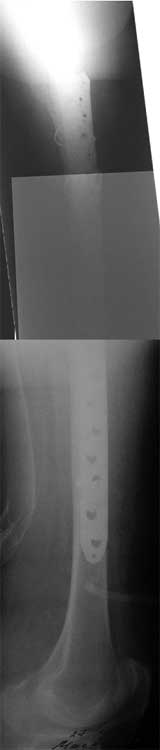

Представленные снимки неудачны ни по качеству, ни по обзорности. Классификационно предположительно Ванкувер В2. Накостный остеосинтез LCP с использованием монокортикальной фиксации в проксимальном отделе.

1. Представляющей наибольшую ценность из представленной информации следует считать фасные снимки №3и №4 (если считать по порядку). На снимке №3 не видны ни проксимальный отдел бедра с зоной (линией) перелома - наложение тени, ни дистальная зона (линия) перелома - область не захвачена. Снимок №4 демонстрирует дистальную линию перелома, но не показывает уровень конца ножки эндопротеза. В таких сучаях как способ можно выполнять снимок "с метками" - чтобы при при наложении снимков на негатоскопе иметь целостностное представление о всём сегменте от тазобедренного до коленного суставов.

2. Не совсем так. Перелом В2 (по C. Duncan и B.A.Masri, 1995) - перелом на уровне ножки эндопротеза или непосредственно дистальнее её конца с нестабильностью ножки, но хорошим качеством кости проксимального отдела бедра. Как известно, по статистике - наиболее часто встречающийся тип перипротезного перелома при первичном эндопротезировании. Очевидно - продольное раскалывание проксимального фрагмента в данном случае вызовёт нестабильность ножки.

Вот фрагменты этих снимков с более различимыми областями интереса.